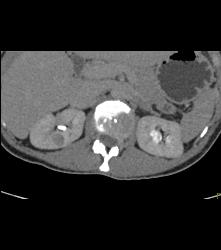

Subtle 1cm Renal Cell Carcinoma Best Seen on Late Phase Images- See Full Sequence for Best Definition